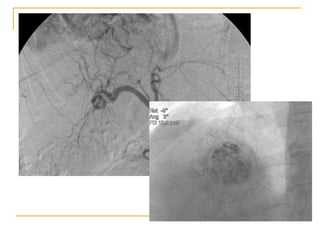

cTACE-conventional transarterial chemoembolization Administration of chemotherapeutic agent mixed with ethiodal prior to arterial obstruction with embolic beads. Ethiodal is selectively retained within the tumor and prolongs chemotherapy dwell time.

Mechanism of cTACE

HCC exhibits intense new-angiogenic activity with blood supply progressing from the portal vein to the hepatic artery

Chemotherapy delivered in high concentration enhances coagulative tumor necrosis

Arterial obstruction results in ischemic tumor necrosis with a high rate of objective response

Perfusion to uninvolved liver is maintained by the portal vein permitting selective targeting of tumor